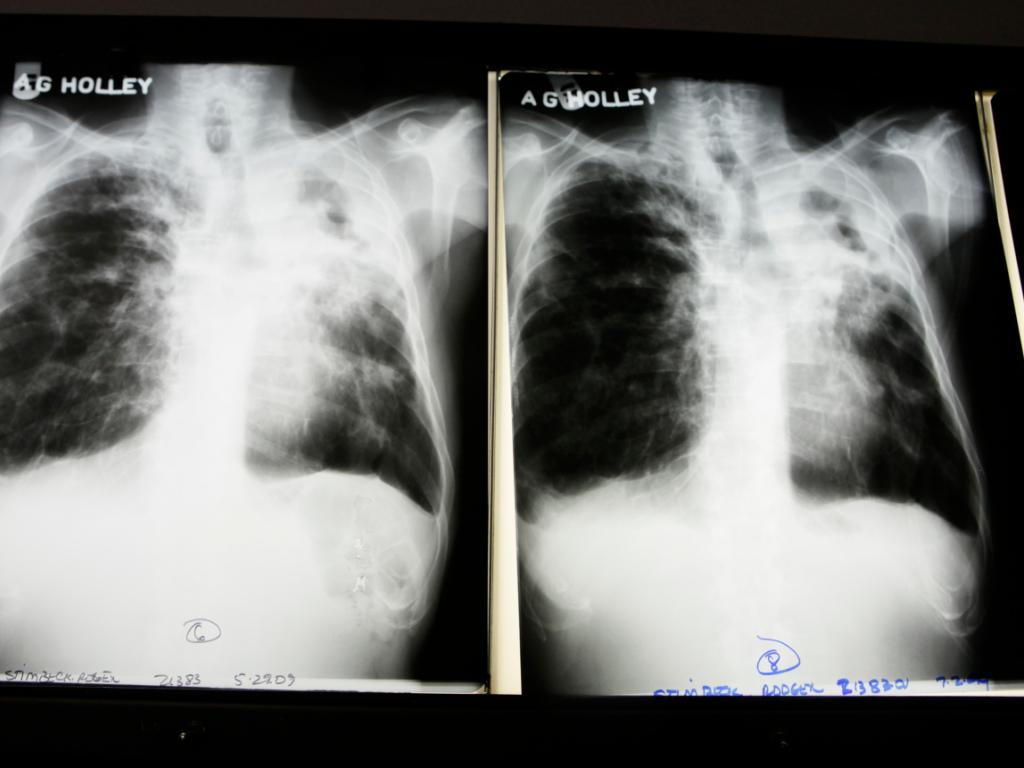

Neuer resistenter Tuberkuloseerreger bei Flüchtlingen entdeckt

(Keystone-SDA) Das Institut für Medizinische Mikrobiologie der Universität Zürich hat einen neuen multiresistenten Tuberkuloseerreger entdeckt. Der Keim wurde 2016 an insgesamt acht afrikanischen Flüchtlingen nachgewiesen. Daraufhin wurde ein europaweites Alarmsystem aufgebaut.

Das Nationale Referenzzentrum für Mykobakterien (NZM) der Universität Zürich fand im Februar 2016 bei einem somalischen Asylsuchenden aus dem Empfangszentrum Chiasso TI einen resistenten Tuberkulosekeim, der sogar für die Fachleute aussergewöhnlich war. «Der Erreger wies eine neuartige Kombination von Resistenzen gegen vier verschiedene Antibiotika auf, die noch nie beschrieben worden war», sagt Peter Keller, Leiter Diagnostik im NZM, laut einer Mitteilung der Universität Zürich vom Dienstag.

In den folgenden Monaten wurde der gefährliche Keim bei weiteren Patienten nachgewiesen, die alle aus Ländern am Horn von Afrika nach Europa migriert waren. Insgesamt identifizierte das NZM den Erreger zwischen Februar und November 2016 bei acht Flüchtlingen aus Somalia, Eritrea und Dschibuti.